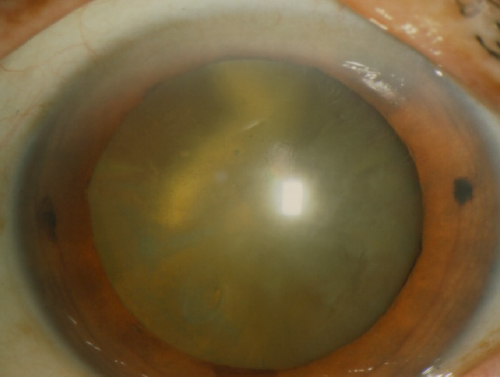

水疱性角膜症

水疱性角膜症とは

角膜の一番奥を内皮といいますが、ここは再生しない組織です。そのため手術や炎症性疾患などで、角膜内皮細胞数が減少すると、角膜に水がたまる(浮腫)ようになります。

進行すると混濁して水疱性角膜症になります。

症状

物がぼやけて見え、さらに進むとやけどの水ぶくれ(水疱)と同じような眼の痛みが続くようになります。

水疱性角膜症(術前)

角膜内皮移植後10か月、視力は(1.0)